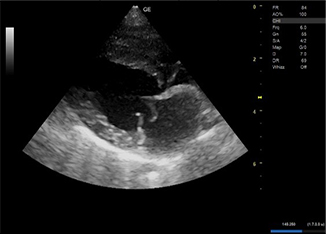

明らかな腹水貯留は認められなかった。 - 心エコー図検査にて、僧帽弁の逸脱とそれに伴う僧帽弁逆流が認められた。